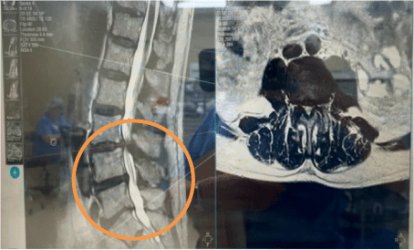

L3-4 stenosis, mild spondylolisthesis and instability

The patient underwent a L3-4 decompression and interbody fusion to relieve pain, stabilize the area, and restore quality of life. The physician elected a posterior Cortical Bone Trajectory (CBT) technique for screw placement due to the many benefits it offers including optimal screw purchase into high-density bone, small incision, less muscle retraction, lower blood loss, shorter surgical time, and directional avoidance of neural anatomy.1 Achieving a precise trajectory is critical in this technique to achieve optimal cortical bone purchase and to prevent a breach of the lateral mass of the vertebral body.

The use of CBT trajectory requires increased accuracy due to the narrow anatomical placement corridor. In this case, the Bolt Navigation System allowed precise placement of cortical screws with a more confined midline surgical access with a straight-on, slightly cranial and divergent screw angulation away from neural elements. Further, it provided fixation through the medial and lateral portions of the cortex providing advanced bony purchase.